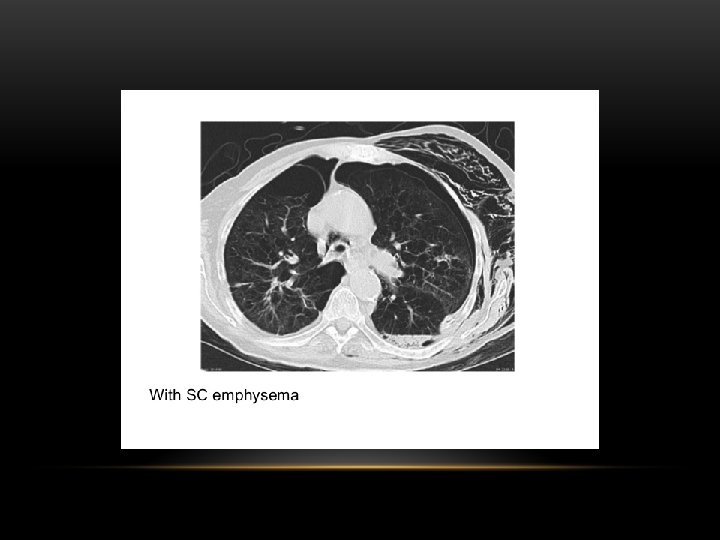

Pneumothorax is air in the pleural space. Radiological criteria: Air (black) in pleural space. No lung markings in pleural space. Recognition of atelectatic lung (lung margin). The lung recoils to a resting state as the negative pressure in the pleura is lost (relaxation atelectasis).

Shift of mediastinum to the opposite side. The mediastinum is held in the middle by balance between pleural pressures. When the negative pressure on the side of the pneumothorax is lost, the mediastinum gets pulled by the normal negative pressure from the opposite side. Progressive shift subsequently could result from a push secondary to tension pneumothorax. Opposite lung gets the entire cardiac output and the vascular markings become prominent.

Tension pneumothorax : is the progressive build-up of air within the pleural space, usually due to a lung laceration which allows air to escape into the pleural space but not to return. Positive pressure ventilation may exacerbate this 'one-way-valve' effect. Progressive build-up of pressure in the pleural space pushes the mediastinum to the opposite hemithorax, and obstructs venous return to the heart. This leads to circulatory instability and may result in traumatic arrest.

Causes of pneumothorax: -Burst small blebs o bullae. -Empyema -Trauma -Certain forms of interstitial pulmonary disease -Pneumocytosis carinii pneumonia -Metastasis (rarely)